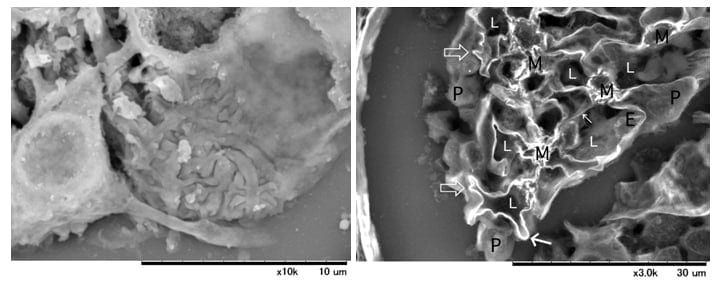

在FSGS病理切片中观察到肾小球的LV-SEM像

左(表面):Platinum-blue染色、右(截面):PAM染色

稻贺教授指出“低真空SEM和传统TEM、光学显微镜主要的区别是:它可以实现立体观察和三维成像。”“Alport综合症是在基底膜形成网状结构,之前我们一直采用TEM观察切片的二维图像来判断是否发生病变,如篮状细胞的观察,现在我们可以使用低真空SEM观察它真实的三维结构。”

Alport综合症为遗传性疾病,其主要特征是肾小球基底膜发生病变。薄基底膜肾病也是由于肾小球基底膜发生病变引起的,Alport综合症患者往往在青壮年时期发展至终末期肾脏病,必须通过透析进行治疗。这两种肾病的鉴定对于患者的治疗和预后等具有十分重要的意义。冈田教授提到,“过去我们利用免疫染色或透射电子显微镜进行肾病鉴定,现如今诊断技术已实现遗传基因检测,尽管如此,还是不能诊断出肾病类型,而低真空SEM可全面获取标本数据,快速且准确诊断肾病”。

“光学显微镜一般可以观察3微米,最厚5微米的样品,而低真空SEM在这个厚度可以实现三维观察,这样一来可以获取更多的数据信息。我们生活在三维空间,二维角度观察标本确实是维度较低。从这个层面来考虑,对同一样品进行三维观察时,可以发现许多二维图像无法判断出来的病症。”

图示为Alport综合症患者的肾小球在低真空SEM下的图像(PAM染色)。

低真空SEM下清晰呈现基底膜的网状结构。